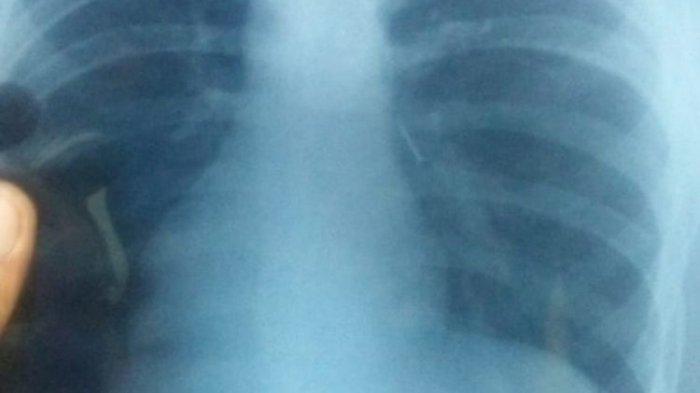

Hasil foto rontgen menunjukkan paku bersarang di tubuh Deni, siswa SMP 2 Parigi, Kabupaten Pangandaran yang tak sengaja menelan paku.

Deni Nugraha (13), Murid SMP 2 itu, tanpa sengaja menelan paku styrofoam saat pamer sulap di hadapan teman-temannya.

Alhasil bocah tersebut harus dilarikan ke rumah sakit untuk menjalani operasi untuk pengangkatan paku yang bersarang di paru-paru Deni.

"Ternyata ini pakunya masuk saluran pernafasan, jadi ke paru-paru," kata Yuli.